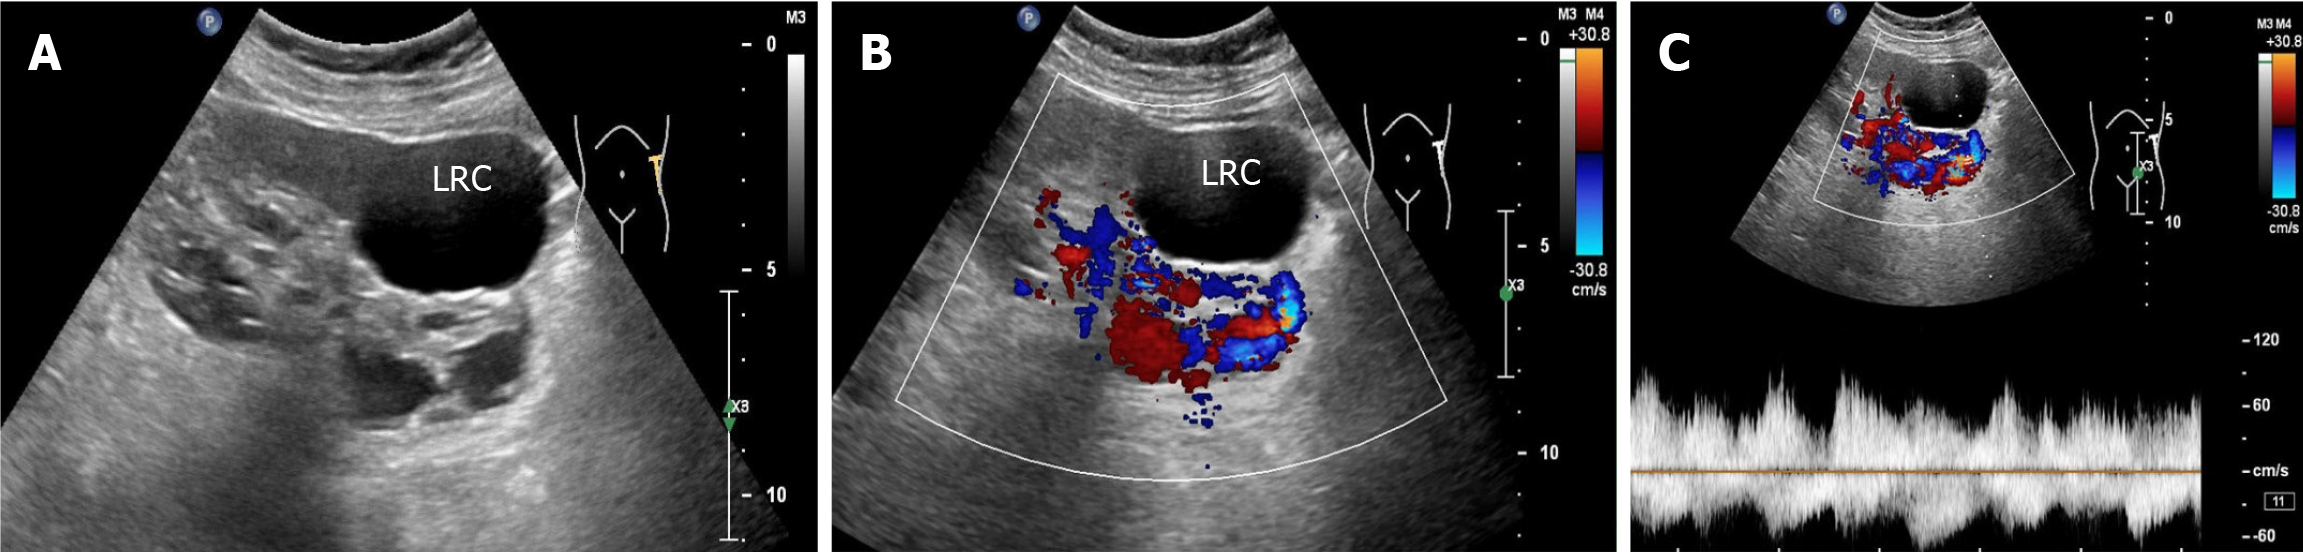

Renal ultrasonography revealed the possible presence of left RAVF in the kidney. To confirm the existence of RAVF outside the kidney, renal vascular ultrasonography was performed. 2D images revealed that the left renal vein was widened and uneven in thickness, with an internal diameter of 1.8 cm at the widest point (Figure 3A and B). CDFI re

When the RAVF is relatively small, there is no obvious manifestation on 2D ultrasound images. However, when the fistula is large, arterialization of the affected veins can cause the renal veins to become locally tortuous and dilated on 2D sonograms. The intrarenal veins appear spongy and show localized anechoic areas. In addition, the location and size of the fistula can be observed in 2D images. RAVF color doppler ultrasound reveals abnormal blood flow signals with high speed and turbulence in tortuous and dilated blood vessels. RAVF spectral doppler of blood flow has the characteristics of high speed, low resistance, burrs, and no empty window. This is because the arterial blood flow is shunted through the fistula and directly into the vein, which results in arterialization of venous blood flow.

An arterial-like flow spectrum is detected in the draining vein, which is a characteristic manifestation of ultrasound in diagnosing RAVF[10]. In this case, the patient’s 2D ultrasound images, color doppler, and spectral doppler ultrasound features were consistent with the ultrasound manifestations of RAVF, which supported the diagnosis of left RAVF. However, ultrasound revealed only one more obvious fistula on the outside of one kidney, without revealing the exact size of the fistula within the intrarenal pedunculated vascular mass. Notably, this patient had not only RAVF but also renal cysts in the left kidney. When the 2D ultrasound examination revealed several anechoic areas within or around the kidney, it was impossible to consider it a simple renal cyst based on conventional thinking. In such cases, color doppler flow should be activated. When blood flow signals are found in anechoic areas, spectral doppler should be used to observe the blood flow spectral characteristics to distinguish it from renal cysts. Color doppler ultrasound can easily distinguish RAVF from renal cysts. For anechoic lesions near the renal hilum in the central region of the kidney, especially small asymptomatic lesions, ultrasound may present a risk of missed diagnosis. Second, for patients with hematuria, in addition to considering common stones and tumors, ultrasound physicians should also consider renal vascular abnormalities as one of the rare causes of hematuria. In particular, when 2D sonography shows cystic lesions in the kidney, CDFI should be initiated to identify vascular abnormalities. The hematuria in this patient was caused by left RAVF, not by a left renal cyst.